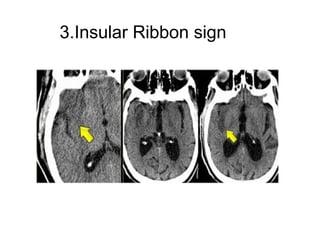

3.Insular Ribbon sign

• This refers to hypodensity and swelling of

the insular cortex.

It is a very indicative and subtle early CT-

sign of infarction in the territory of the

middle cerebral artery.

It has to be differentiated from herpes

encephalitis.